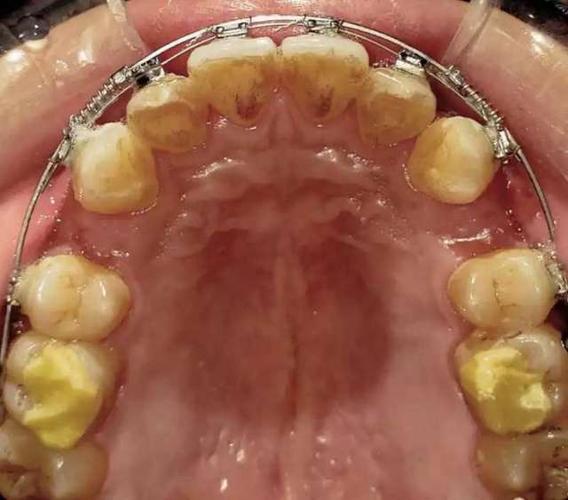

第二个密码是“生物力学,精准控根”,正畸的本质是牙齿在生物力学作用下的移动,梅志强对此的解析尤为透彻,他详细拆解了不同牙齿移动类型(如整体移动、压低、伸长、旋转)对应的托槽定位、弓丝选择及加力方式,在实现上颌磨牙远中移动时,他会对比传统滑动法与种植体支抗法的力学差异,强调“轻力持久”原则,避免牙根吸收;在关闭拔牙间隙时,通过“T型曲”“摇椅弓”等工具的力学特性分析,说明如何控制前牙转矩与后牙支抗,视频中的动画演示常配合力学公式,帮助学习者理解“力-力矩-中心”的平衡关系,让技术操作不再是“照葫芦画瓢”,而是基于力学原理的精准调控。

第三个密码是“患者共情,长期管理”,梅志强始终将“人”置于正畸治疗的核心,视频中不仅展示技术,更传递与患者沟通的智慧,他强调治疗前需充分告知患者治疗目标、周期及潜在风险,通过“治疗前-中-后”对比照片、模拟效果视频等方式,建立患者的信任与配合度,在治疗过程中,他注重患者的舒适度,如调整托槽位置避免黏膜刺激、使用隐形矫治器提升美观性;在保持阶段,则根据牙齿稳定性数据,设计个性化保持器方案,并通过定期随访表格追踪复发风险,体现“治疗结束不等于服务终止”的理念。